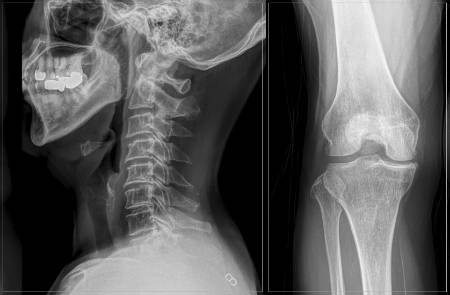

척추·관절 질환은 하나의 병이 또 다른 병을 부르는 경우가 다반사다. 한 부위에 이상이 생기면 이를 보완하기 위해 다른 부위에 연쇄적으로 부담이 가기 때문이다. 허리 통증으로 병원을 방문했다가 무릎의 문제가 더 심해 먼저 치료받기도 한다. 특히 고령층은 퇴행성 변화로 두 부위에서 동시에 통증이 나타나는 경우가 잦다. 바른세상병원 척추센터 박재현 원장(신경외과 전문의)은 "척추와 관절 치료를 병행하는 환자는 10명 중 6명 정도"라고 말했다.

특히, 척추관협착증은 무릎 연골이 닳아 염증이 생기는 무릎 퇴행성 관절염과 헷갈리기 쉽다. 무릎이 망가지면 걸음걸이가 바르지 못하고 걷다 서기를 반복하는데, 이 과정에 척추 건강이 나빠지며 증상이 악화하는 악순환이 반복된다. 통증을 줄이기 위해 자세가 틀어지거나 양반다리, 짝다리 등을 자주 취해도 골반 불균형을 초래할 수 있다. 체형 변형은 물론 허리디스크, 척추측만, 고관절 통증의 '씨앗'이 될 수 있다는 의미다.

고관절염은 노화와 함께 연골이 마모돼 염증과 통증이 발생하는 질환이다. 고관절은 골반과 대퇴골을 연결하는 관절로 걷기, 앉기, 일어서기 등의 자유로운 움직임을 책임진다. 고관절염이 오면 골반 부위 통증과 다리 회전 시 불편함을 느끼고 걸을 때 절뚝거리기도 한다. 퇴행성 고관절염이 진행되면 엉덩이 부근에 통증이 느껴지는데, 이 통증이 허리 질환과 유사해 환자 스스로는 감별하기가 쉽지 않다.

실제 목디스크 환자는 직접적인 목 통증보다 어깨나 팔 등 다른 곳에서 증상이 시작되는 사례가 많다. 목덜미나 어깨 위쪽의 통증이 가장 흔하고 팔과 어깨 저림, 손가락 끝까지 저림이 타고 내려오는 증상이 나타나기도 한다. 심한 경우 척수 손상으로 다리의 힘이 약해지거나 마비가 발생하기도 한다.